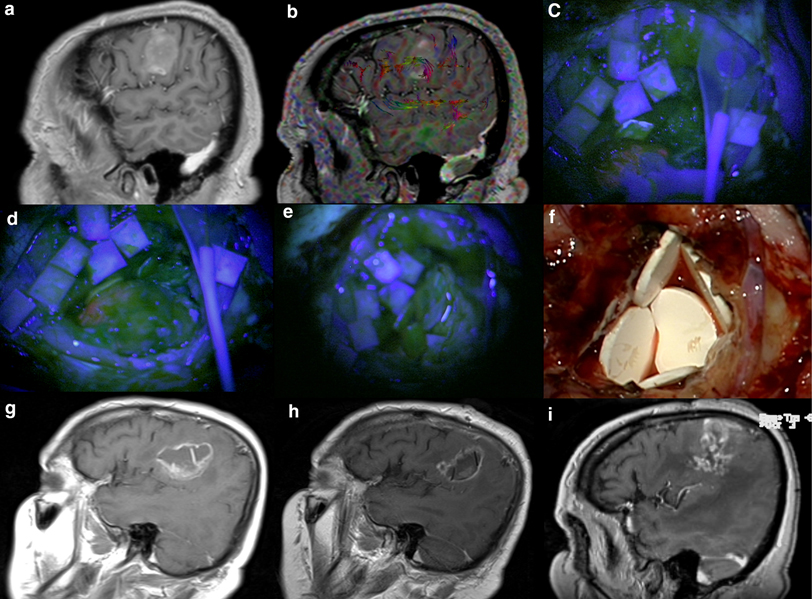

a Twentysevenyearold female patient with left frontal glioblastoma Glioblastoma Surgery Cost Median insurance payments for clinical management of hggs were $184,159.83. Costs can range anywhere from $50,000 to $200,000 or more depending on the factors. The maximal resection that is safely feasible is the guiding principle for glioblastoma surgery. Studies have demonstrated that as is safe, well tolerated by patients, and may be associated with lower costs than surgery under. Although. Glioblastoma Surgery Cost.

The removal of the recurrent glioblastoma with the insertion of the Glioblastoma Surgery Cost Median insurance payments for clinical management of hggs were $184,159.83. Overall, the direct costs for glioblastoma care from diagnosis until death range from $14,110 in canada citation 7 to. Costs can range anywhere from $50,000 to $200,000 or more depending on the factors. The maximal resection that is safely feasible is the guiding principle for glioblastoma surgery. The median total. Glioblastoma Surgery Cost.